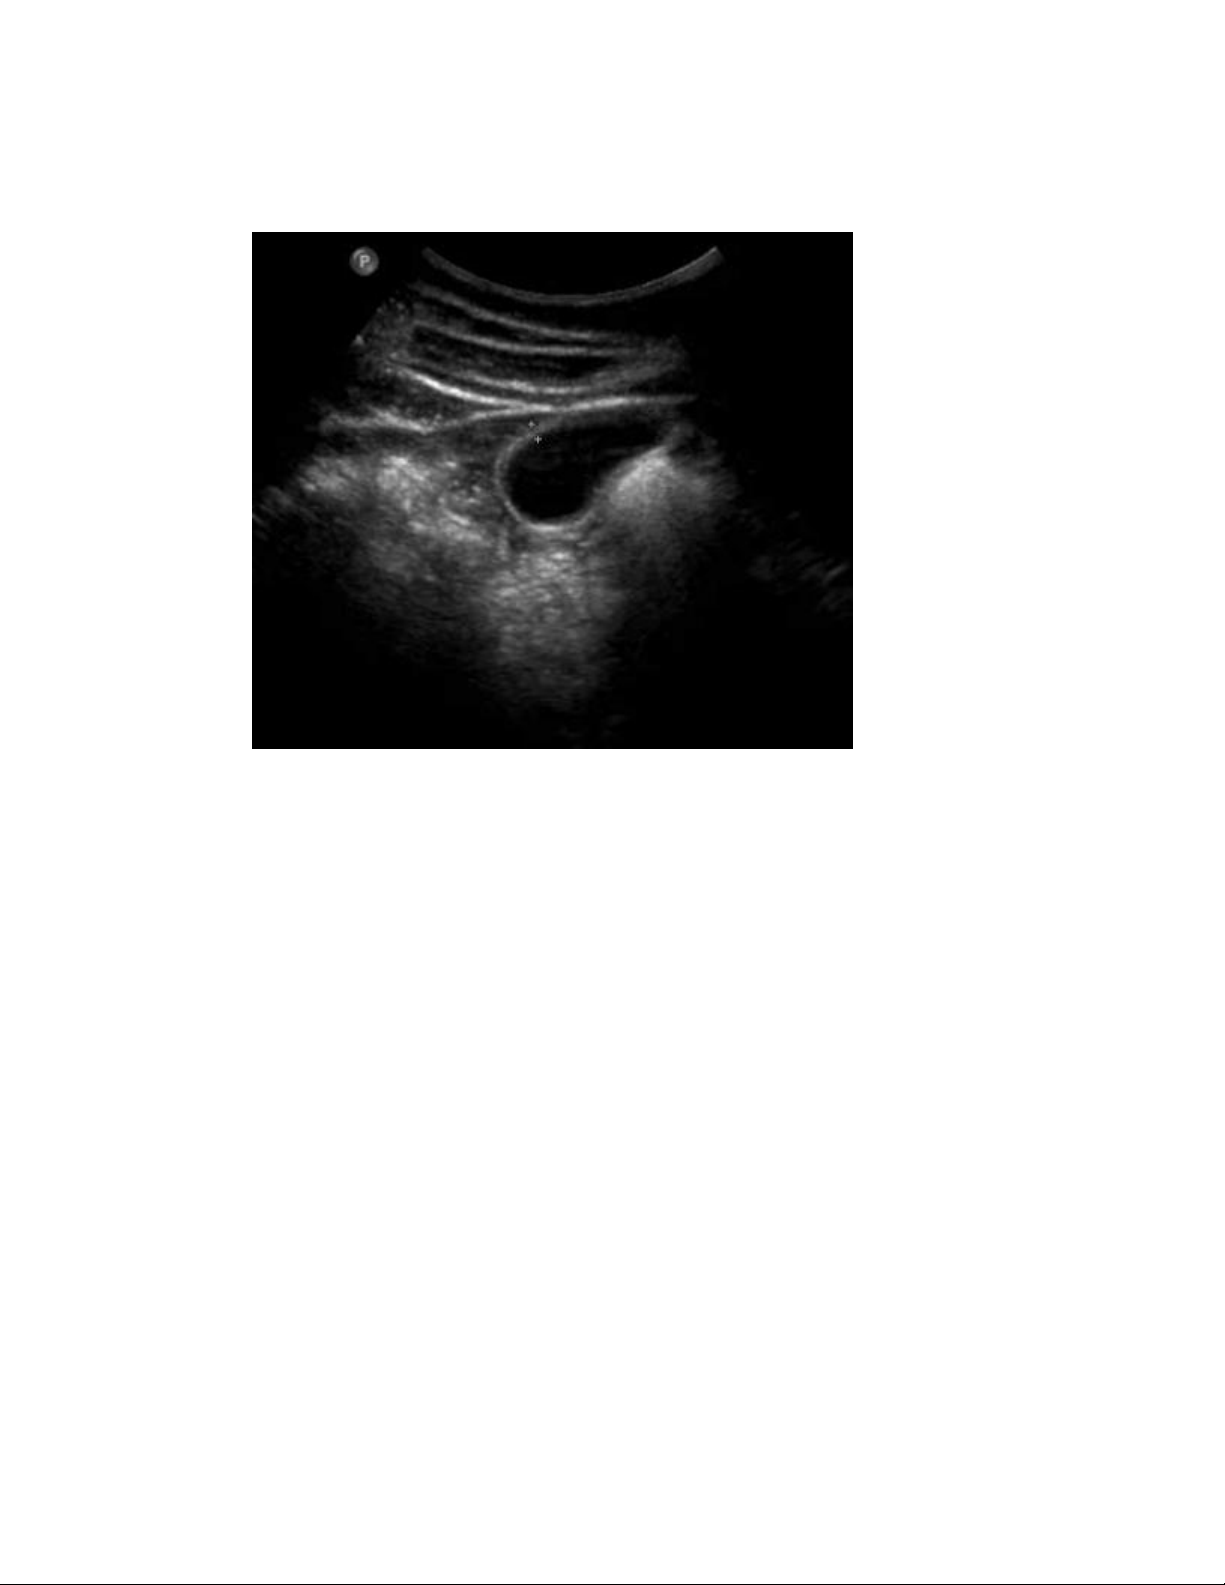

Hình cắt dọc túi mật

Có khối hồi âm dày hình chiếc lá bên trong túi mật có kích thước 2.8 x 0.9

x 1.0 cm.